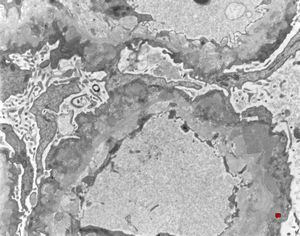

M,53y. | type III membranoproliferative glomerulonephritis